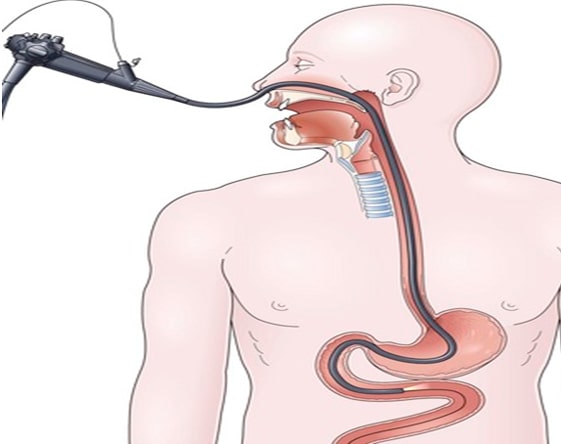

Endoscopy Training: Basic

1-month course in diagnostic UGI/ LGI endoscopy

Endoscopy Training: Advance

1-month course in therapeutic endoscopy

Painless endoscopy is one of the advanced procedures adopted for diagnosing the abnormalities in the stomach, particularly the small intestine. SR Kalla Hospital has a team of trained doctors, anesthetists, and the latest equipment to perform this endoscopic procedure. The major benefit of this procedure is that the patient does not experience any major discomfort.

ERCP is a procedure that is adopted to diagnose the disease-related liver, gallbladder, pancreas, and biliary system. With a help of a special endoscope, the inside of the digestive system is examined. Laser Lithotripsy is an advanced procedure that uses a laser to break down the stones found in the ureter, kidney, and gallbladder.